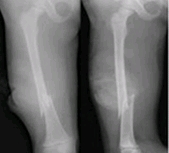

그 정도에 따라 뼈에는

골감소증이나 골다공증이 발생하게 됩니다.

이러한 골다공증이 생기면 뼈가 아프고,

가벼운 충격에도 쉽게 뼈가 부러질 수 있고,

그로 인해 통증이 발생할 수 있습니다.